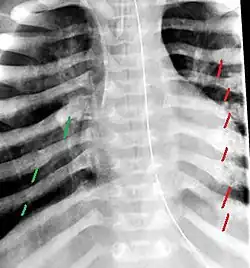

The material factual allegations of the amended complaint are as follows. Plaintiff was born on May 14, 1970. On repeated occasions during the first year of her life she was severely beaten by her mother and the latter's common law husband, one Reyes. On April 26, 1971, when the plaintiff was eleven months old, her mother took her to the San Jose Hospital for examination, diagnosis, and treatment. The attending physician was defendant Dr. Flood, acting on his own behalf and as agent of the defendant San Jose Hospital. At the time, the plaintiff was suffering from a comminuted spiral fracture of the right tibia and fibula, which gave the appearance of having been caused by a twisting force. Plaintiff's mother had no explanation for this injury. Plaintiff had bruises over her entire body. In addition, she had a non-depressed linear skull fracture which was then in the process of healing. Plaintiff demonstrated fear and apprehension when approached. Inasmuch as all plaintiff's injuries gave the appearance of having been intentionally inflicted by other persons, she exhibited the medical condition known as the battered child syndrome.

It is alleged that proper diagnosis of plaintiff's condition would have included taking X-rays of her entire skeletal structure, and that such procedure would have revealed the fracture of her skull. Defendants negligently failed to take such X-rays, and thereby negligently failed to diagnose her true condition. It is further alleged that proper medical treatment of plaintiff's battered child syndrome would have included reporting her injuries to local law enforcement authorities or juvenile probation department. Such a report would have resulted in an investigation by the concerned agencies, followed by a placement of plaintiff in protective custody until her safety was assured. Defendants negligently failed to make such report.